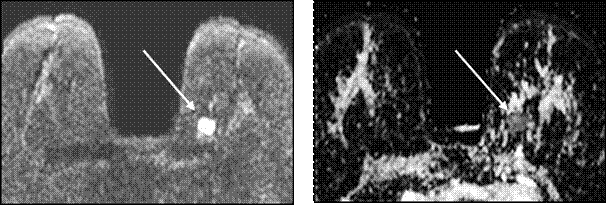

Полученные изображения автоматически обсчитывались с построением карт измеряемого коэффициента диффузии (ADC), который, как известно, зависит от скорости диффузии молекул воды во внутриклеточных и межуточных пространствах, которые имеют различную структуру в нормальной и патологически измененной ткани и косвенно отражает плотность клеток в патологическом очаге (рис. 5).

А Б

Рисунок 5 — МР-маммография. DWI. Стрелкой показано мягкотканое объемное образование в левой МЖ (А). На ADC карте стрелкой показано это же мягкотканое объемное образование, в котором определяется ограничение диффузии (Б).

Как известно, нормальная ткань МЖ имеет высокие значения ADC (2,09±0,27х10-? мм?/с), поскольку вода проходит через нее относительно свободно, в то время как в большинстве видов солидных злокачественных образований ADC снижен, потому что опухолевые клетки более плотно расположены, межклеточные пространства практически отсутствуют и скорость диффузии молекул воды снижается.

Критерием наличия злокачественного процесса являлось пороговое значение ADC 1,20х10-? мм?/с. Однако мы учитывали, что ограничение диффузии (снижение значений ADC) встречается и при высоком содержании протеина в жидкости, например при абсцессе МЖ.